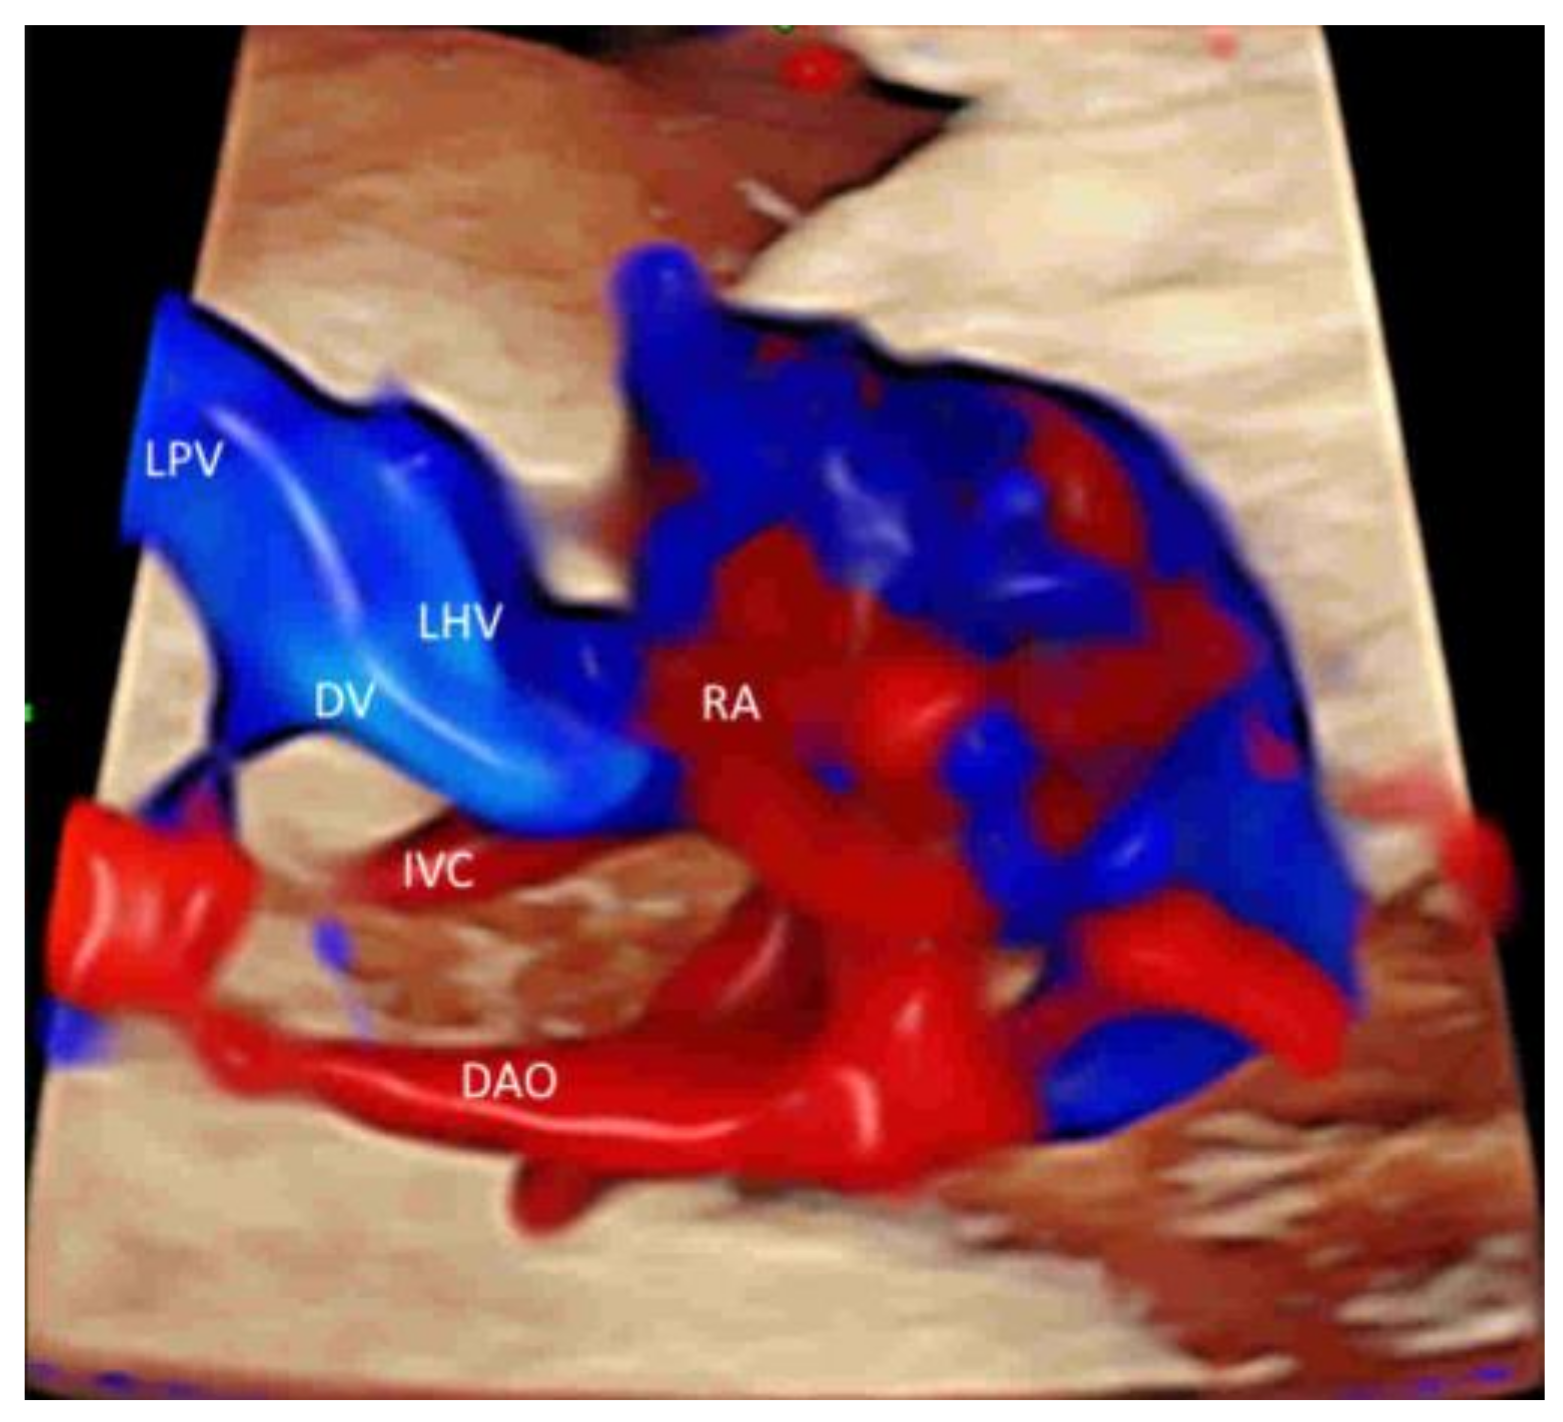

- Gindes, L.; Pretorius, L.H.; Romine, L.E.; Kfir, M.; D’Agostini, D.; Hull, A.; Achiron, R. Three-Dimensional Ultrasonographic Depiction of Fetal Abdominal Blood Vessels. J. Ultrasound Med. 2009, 28, 977–988. [Google Scholar] [CrossRef]

- Leung, K.Y. Imaging of fetal precordial venous system by four-dimensional ultrasound with spatiotemporal image correlation technology. J. Clin. Ultrasound 2021. [Google Scholar] [CrossRef]